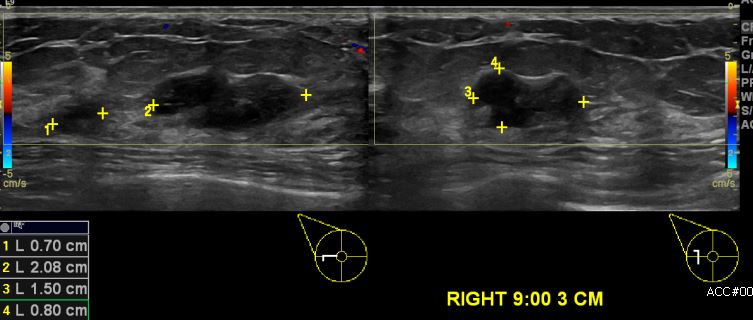

상기환자 우측 유두 분비물로 내원하신 60대 여성분으로 초음파상 우측 9시 방향에서

3cm 떨어진 거리의 의심스러운 멍울 조직검사 시행하여 우측 침윤성 유관암 진단되었습니다.